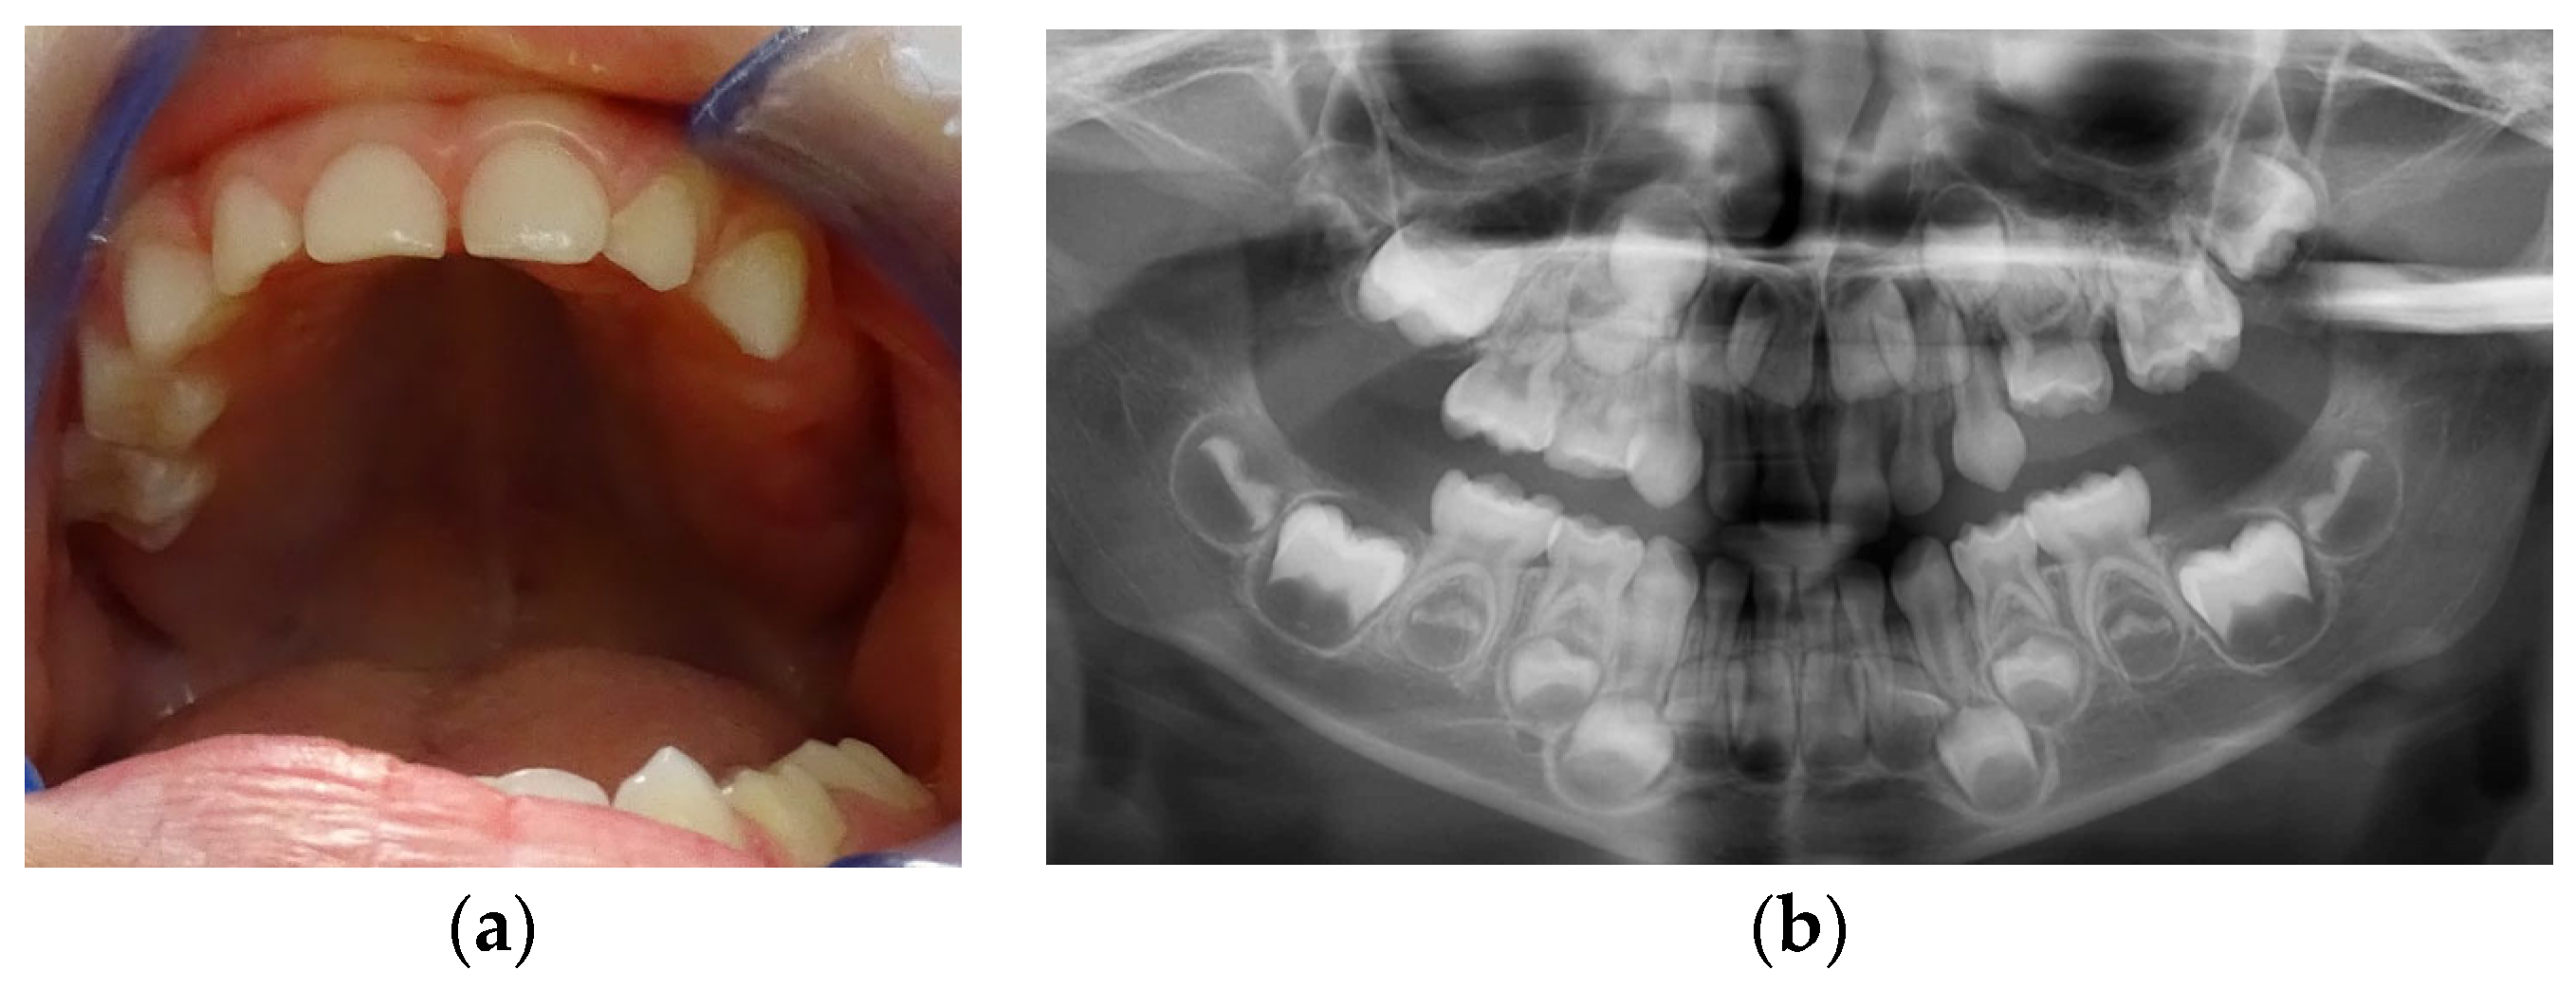

Clinical examination (Figure 1a) revealed no erupted teeth distal to the left upper canine, a left lateral open bite, and a slight shift of the upper midline to the left. Panoramic X-rays taken at this time showed delayed intraosseous development of the lateral left upper teeth as compared to the right side (Figure 1b) and no sign of mechanical obstruction. The agenesis of upper left premolars (24 and 25) was suspected but uncertain at the time.

Figure 1.

First visit; age of 4 y and 4 m. (a) Clinical aspect of the upper arch: no erupted teeth distal to the left upper primary canine; (b) panoramic X-ray.